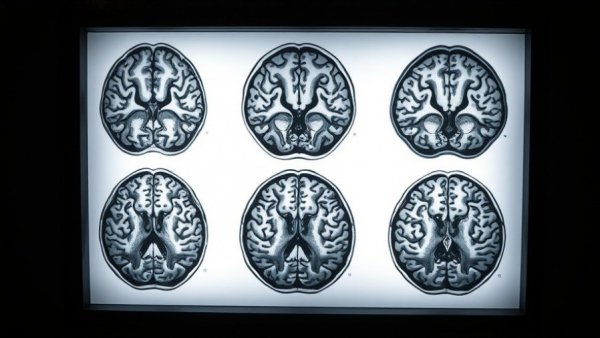

Astrocytomas arise from astrocytes, a type of glial cell in the brain and spinal cord. They vary in severity from benign tumors to aggressive forms like glioblastoma. Grade 3 astrocytomas are particularly notorious for their rapid growth and resistance to conventional therapies. The STELLAR trial focused on the recurrent cases of this category, where traditional chemotherapy and radiation failed to halt progression.